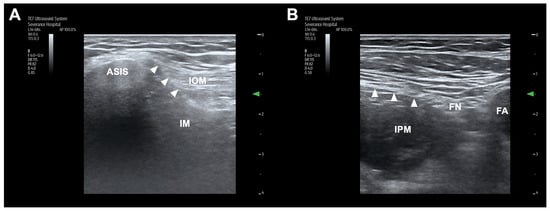

All cadavers were placed in the supine position, and injections were performed by a single experienced anesthesiologist specializing in regional anesthesia and pain medicine. A TE7 ultrasound unit (Mindray Bio-Medical Electronics, Shenzhen, China) with a high-frequency linear probe (4–16 MHz) was used. The ultrasound-guided S-FICB procedure followed the standard protocol (Figure 1A) []. The ultrasound probe was positioned longitudinally at the level of the anterior superior iliac spine and was moved medially to identify the fascia iliaca and sartorius, iliopsoas, and internal oblique muscles. After identifying the ‘bowtie sign’ formed by the muscle fasciae, an 80 mm 22-gauge needle was introduced 1 cm cephalad to the inguinal ligament. Using an in-plane approach, the needle tip was positioned beneath the fascia iliaca, and hydrodissection was used to separate the fascia iliaca from the iliacus muscle. The needle was further advanced in this space in a cranial and slightly dorsal direction. Correct needle placement was confirmed on the basis of the separation between the fascia iliaca and the iliac muscle and the presence of cranial spread of injectate beneath the fascia iliaca. After confirming the correct localization of the needle tip, 30 mL or 60 mL of dye solution was injected during a standardized period of 2 min or 4 min, respectively. The dye solution was either a 30.0 mL mixture of 27 mL distilled water, 2 mL latex solution (Duksan, Ansan, Republic of Korea) and 1 mL green ink (Polysciences, Inc., Warrington, PA, U.S.), or a 60 mL mixture of 54 mL distilled water, 4 mL latex solution, and 2 mL green ink.

Figure 1.

Ultrasound anatomy for the suprainguinal (A) and infrainguinal (B) fascia iliaca block. Arrowheads indicate the fascia iliaca. ASIS, anterior superior iliac spine; IM, iliacus muscle; IOM, internal abdominal oblique muscle; IPM, iliopsoas muscle; FN, femoral nerve; FA, femoral artery.

2.2. I-FICB Procedure

The ultrasound-guided I-FICB was performed following the standard protocol (Figure 1B) []. The ultrasound probe was positioned below the inguinal ligament within the inguinal crease and oriented transversely. Several ultrasound landmarks were identified, including the iliac muscle, sartorius muscle, fascia iliaca, FN, and femoral artery. Subsequently, the probe was moved laterally along the fascia iliaca toward its junction with the medial border of the sartorius muscle. An 80 mm 22-gauge needle was advanced in-plane, beginning from the lateral side and progressing medially, finally piercing the fascia iliaca at the point where it intersects with the iliac muscle and the medial border of the sartorius muscle within the inguinal crease. Correct needle placement was confirmed on the basis of the separation of the fascia iliaca from the iliopsoas muscle with the injectate spreading toward the FN medially and the iliac crest laterally. After confirming the correct localization of the needle tip, 30 mL or 60 mL of dye solution was injected during a standardized period of 2 min or 4 min, respectively.